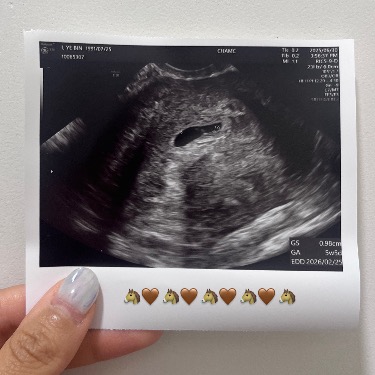

양가 부모님께 손주 소식을 알려 드릴 행복한 준비도 하고, 임테기는 뭔가 민망해서 초음파 사진으로 대체했다. ^^; 저는 명량한 말띠 아기예요! 우리 2월에 만나요~